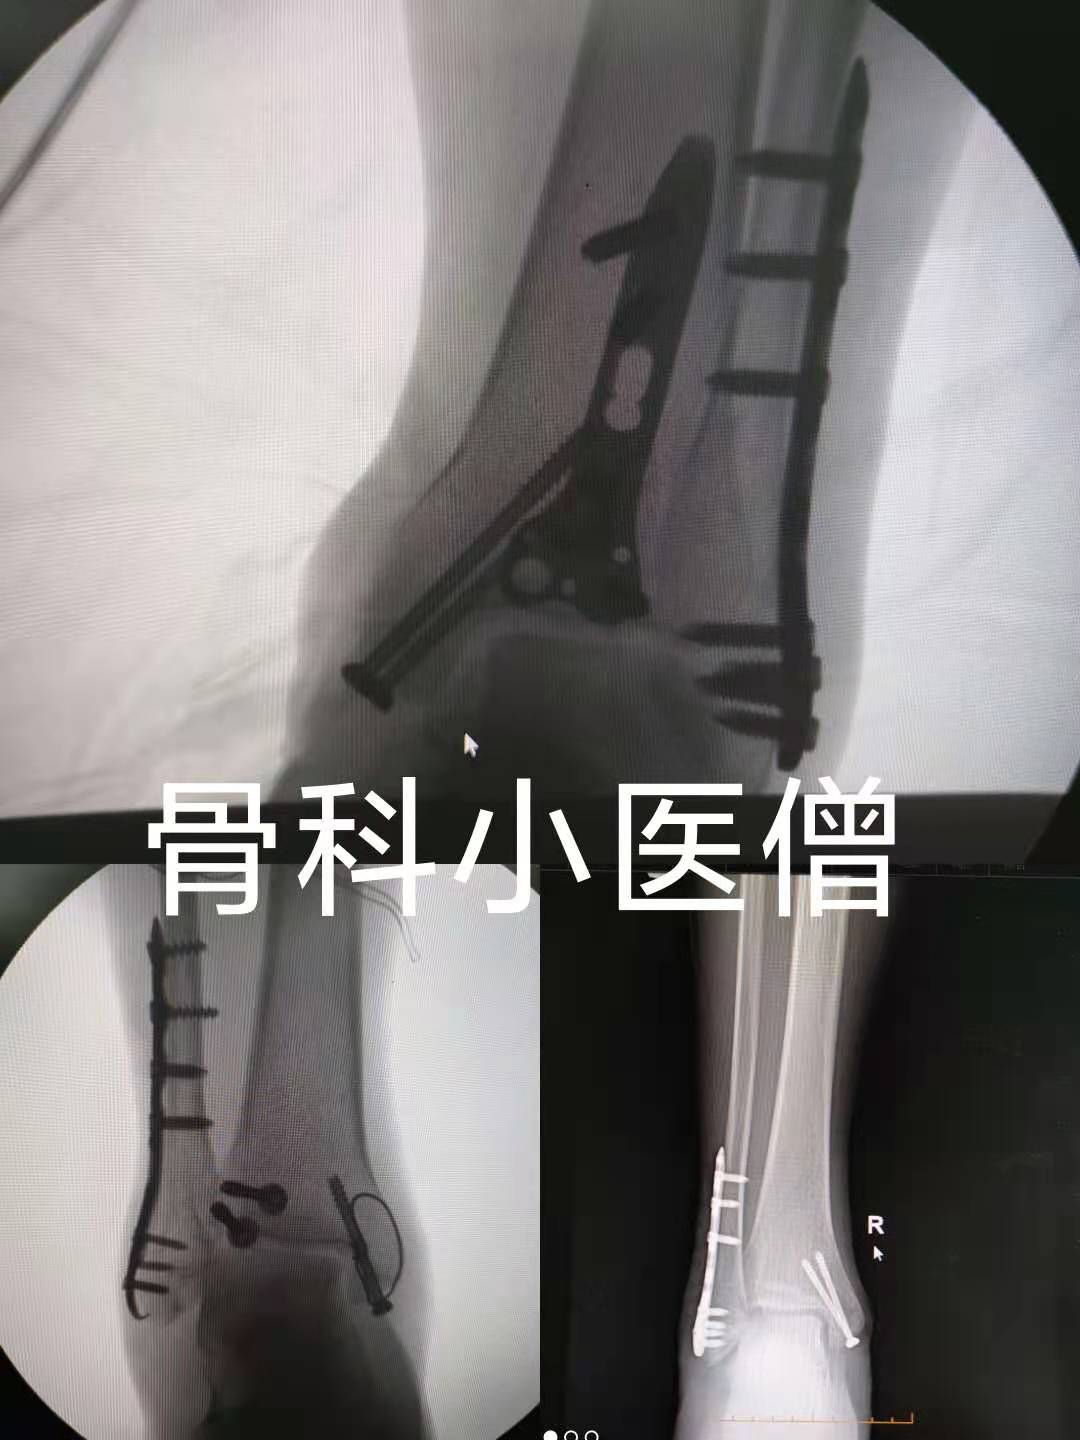

手术治疗:首先需要明确的是:踝关节骨折是否需要手术并不仅仅取决于骨折类型,软组织的条件也至关重要。另外,患者因素如年龄、糖尿病和骨质疏松等情况也可能改变手术指征和固定方法。而一旦手术,最重要的就是取决于怎么样才能更好地重建正常的解剖关系,并维持其稳定。尤其要注意的是:踝关节骨折的理想的手术时机是骨折局部水肿和水疱出现以前。但大多数情况下无法在此之前进行手术,所以,皮内水肿、显著的皮下水肿和水疱的存在均需要推迟手术。

近期几例踝关节骨折术后X线片